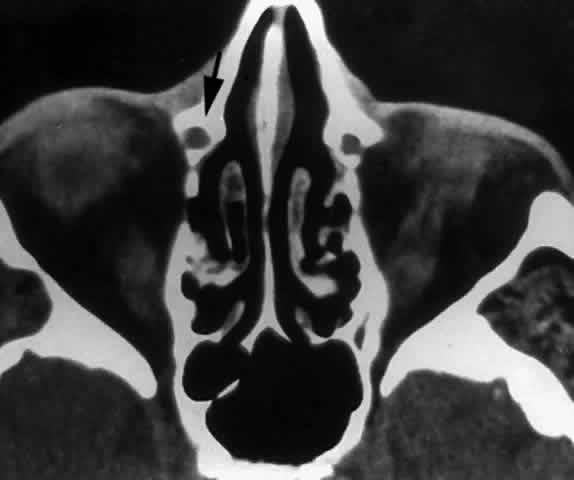

The nasolacrimal canal is a short, bony tube extending inferiorly, laterally, and posteriorly from the lacrimal fossa toward the inferior meatus of the nose. It contains the membranous nasolacrimal duct. The maxillary bone forms the anterior, lateral, and posterior walls of the canal. The medial wall of the nasolacrimal canal is formed superiorly by the descending process of the lacrimal bone, which articulates with the ascending processing of the inferior turbinate bone below. In some cases, the medial wall of the nasolacrimal canal is almost entirely formed by the maxilla (Fig. 29), with a corresponding decrease in contribution from the lacrimal and inferior turbinate bones. This results in a narrowing of the nasolacrimal canal and corresponding nasolacrimal duct.29

Fig. 29. In this computerized tomographic scan of the orbit, the medial wall of the nasolacrimal canal is almost entirely formed by the maxilla (arrow).